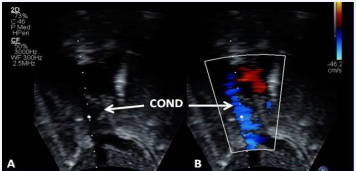

Figure 29 Selected video frame demonstrating wide open conduit (COND) by 2D (A) and color flow imaging (B). Note laminar flow in B indicating no obstruction [69].

Figure 29: Selected video frame demonstrating wide open conduit (COND) by 2D (A) and color flow imaging (B). Note laminar flow in B indicating no obstruction [69].Figure 30 Selected video frames demonstrating connection between the inferior vena cava (IVC) and the conduit (C) by 2D (A) and color flow imaging (B); note that the IVC–C junction is wide open [69].